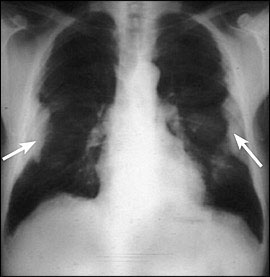

figure1

ひどい石綿症を示している胸のコンピュータ断層。

figure2

胸膜プラークを発達させ、前にアスベストの著しい肺実質の再構築と組織破壊(蜂窩肺)

曝露経験のある患者の胸部X線。

B良性胸膜疾患 benign pleural disease